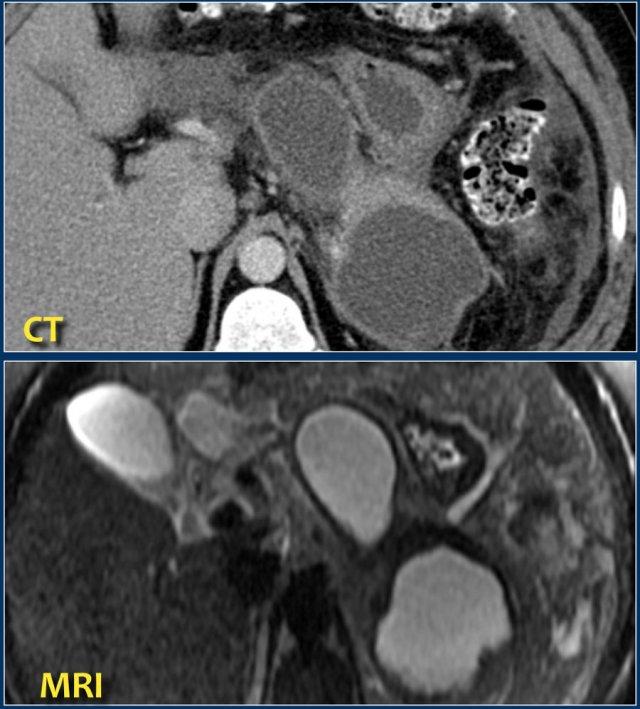

Đây là một bệnh nhân có nhiều ổ dịch quanh tụy đồng nhất trên CT.

Các ổ dịch này cũng cho thấy tín hiệu cao đồng nhất trên chuỗi xung T2W xóa mỡ, được bao bọc hoàn toàn và chứa dịch trong (tức là nang giả tụy).

Bệnh nhân này bị viêm tụy hoại tử cấp tính khởi phát 2 tháng trước.

Hình CT cho thấy một ổ dịch quanh tụy đồng nhất trong mạc treo đại tràng ngang (mũi tên).

Chuỗi xung T2W trên MRI cho thấy ổ dịch có tín hiệu thấp (mũi tên).

Nhiều khả năng đây là tổ chức mỡ hoại tử (tức là hoại tử vô khuẩn hay hoại tử được bao bọc).

Bệnh nhân này không có sốt hay dấu hiệu nhiễm khuẩn huyết.

Dẫn lưu qua nội soi hoặc qua da sẽ có ít hoặc không có tác dụng làm giảm kích thước ổ hoại tử, nhưng lại làm tăng nguy cơ nhiễm khuẩn.